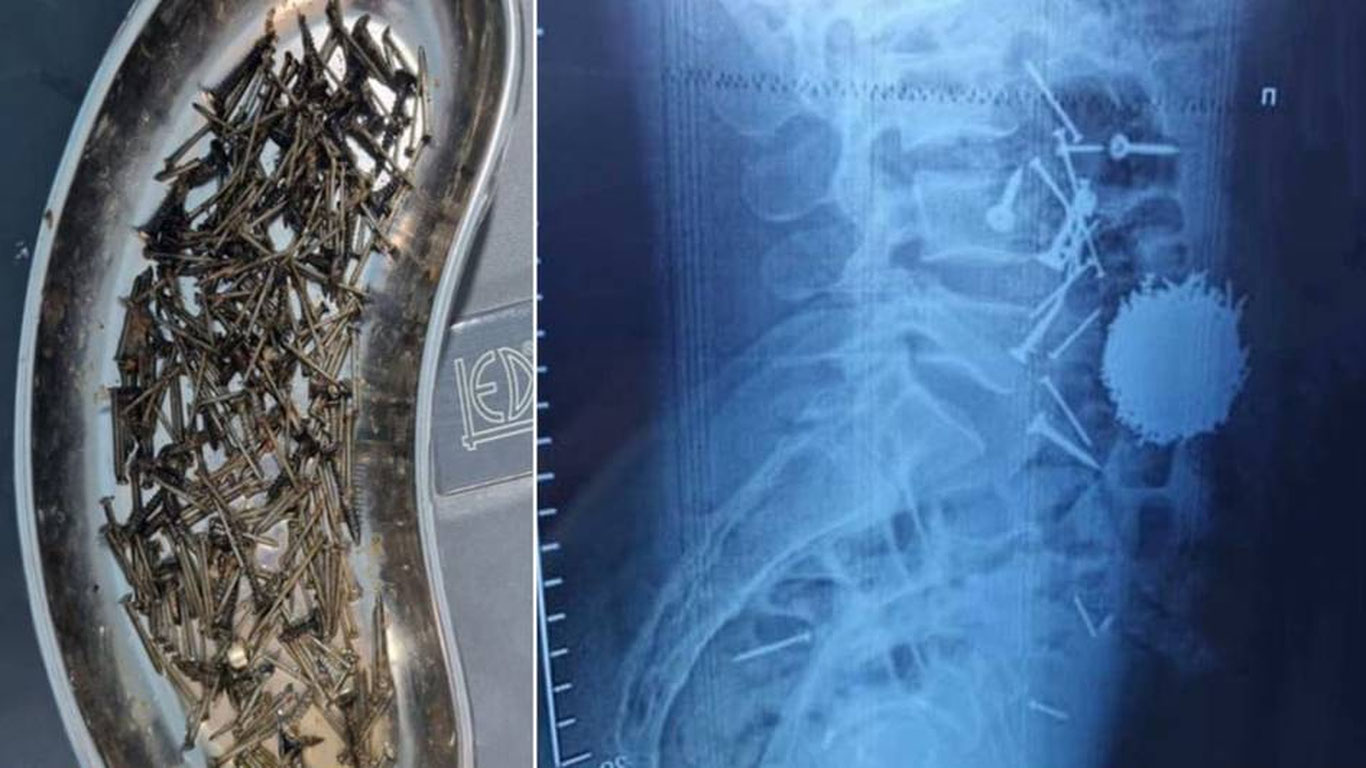

Марказ ахборот хизматининг маълум қилишича, шошилинч қабул бўлимида ўтказилган диагностик ва лаборатор текширувлар натижасида беморнинг ошқозон-ичак тизимида кўп миқдорда металл буюмлар — мих ва саморезлар борлиги аниқланган.

Шифокорлар беморга зудлик билан жарроҳлик амалиёти ўтказиш зарурлиги ҳақида хулоса чиқарган. Олий тоифали шифокор Йўлдош Қулиев раҳбарлигида барча зарур тайёргарлик ишлари амалга оширилиб, лапаротомия ва гастростомия усулида операция ўтказилган.

Жарроҳлик амалиёти давомида беморнинг ошқозонидан умумий оғирлиги қарийб 200 граммни ташкил этувчи металл жисмлар олиб ташланган. Операция бир соатга яқин вақт давом этган.